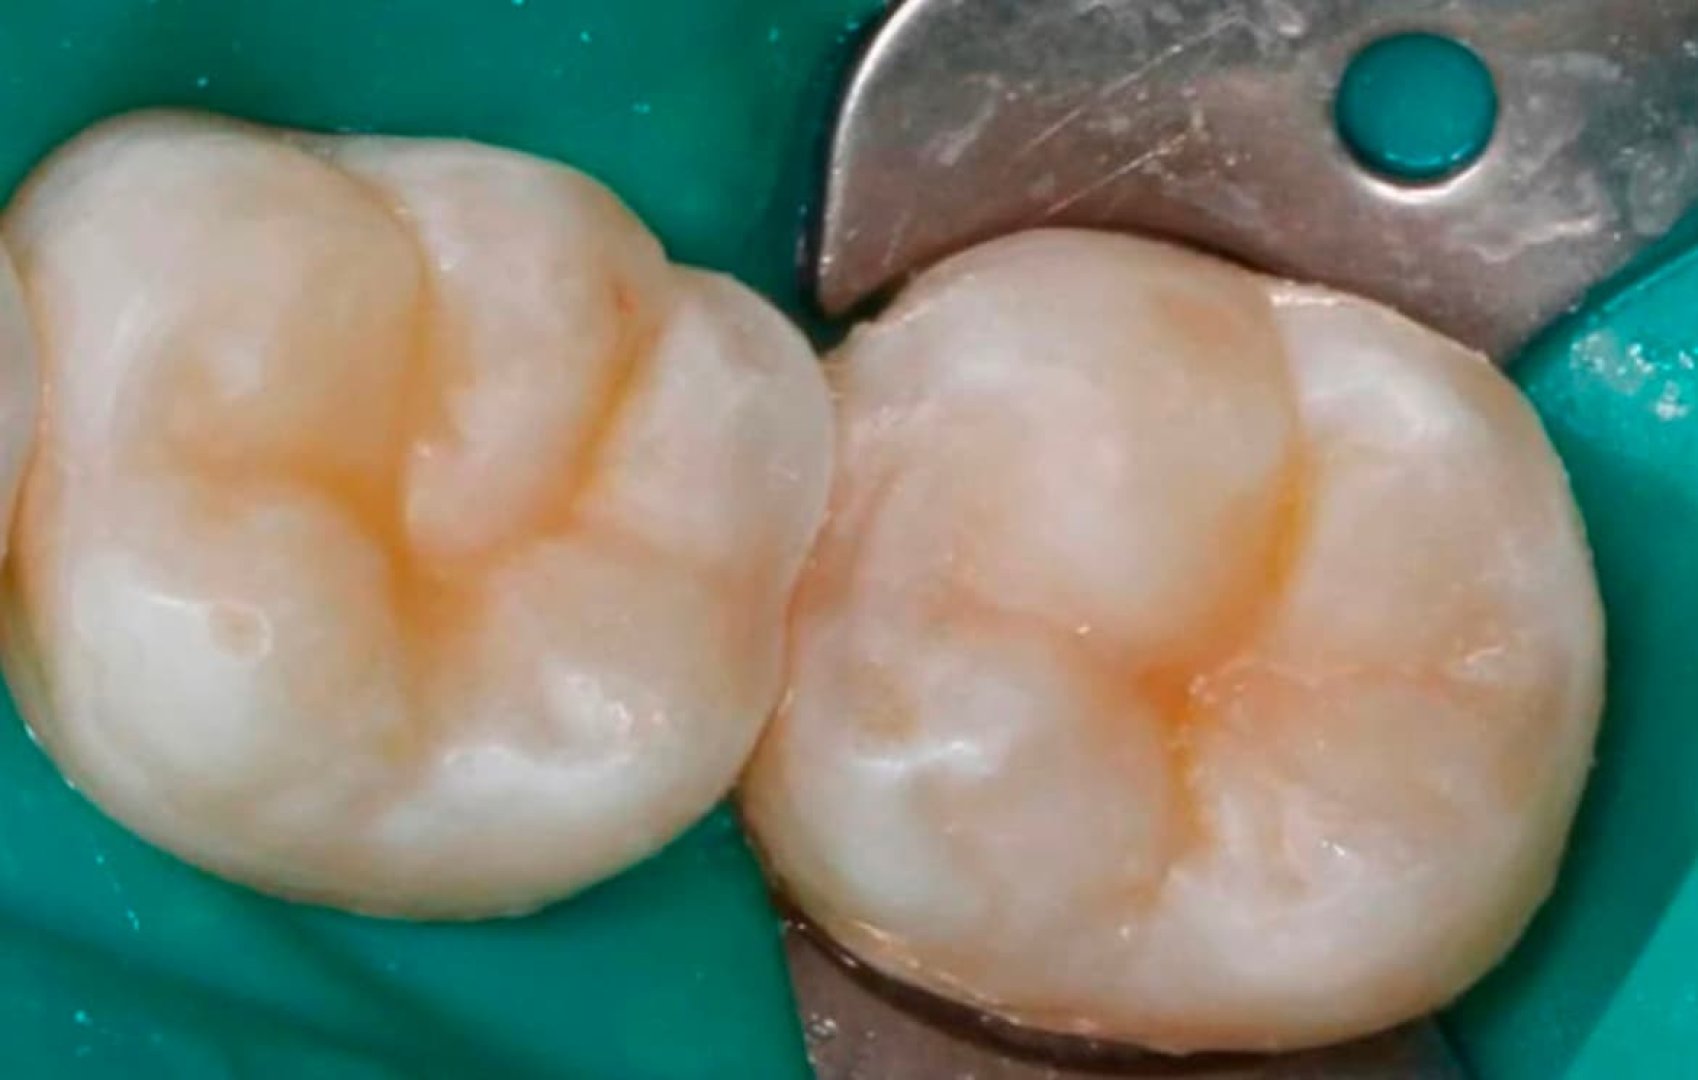

Лечение кариеса, восстановление контактного пункта зуба

Быстрая и безболезненная процедура